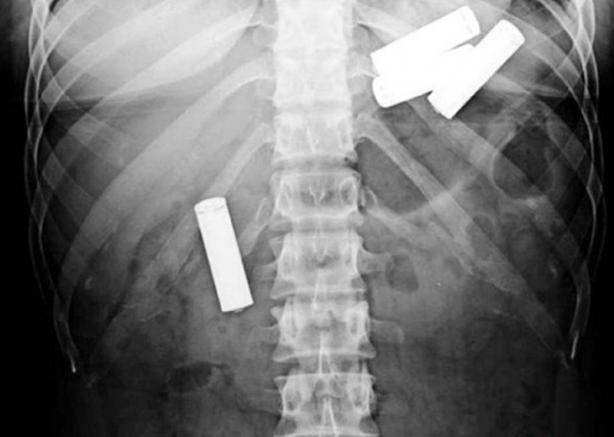

İngiltere'de gümrükte çekilen bu röntgen filminde labrador cinsi bir köpeğin midesine yerleştirilmiş kokain paketleri gözüküyor